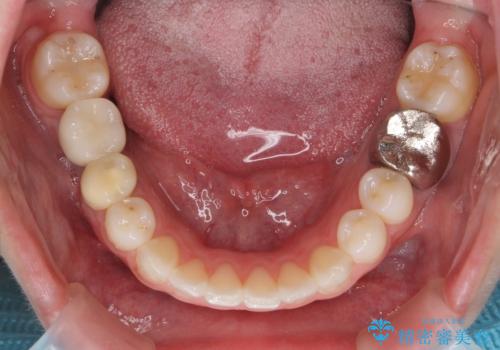

- 前歯のがたつきを主訴に来院。

左上の犬歯が歯肉退縮しており、そこを抜歯して矯正することにしました。

右上については、奥歯をインプラント矯正により後ろに動かして、引っ込んだ前歯を並べるスペースを確保しました。

右下6番については保存不可能であり、矯正治療終了後にインプラント補綴しています。